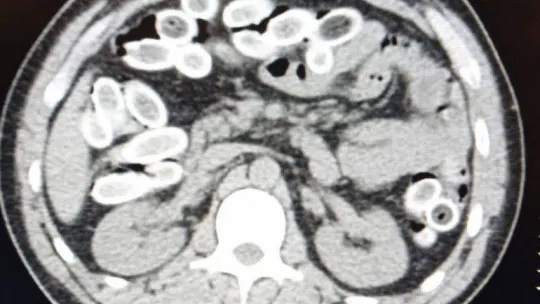

Türkiye’ye midesinde uyuşturucu maddeleri soktuğu tespit edilen zanlı, ardından Yalova Devlet Hastanesi’ne götürüldü. Tomografi cihazı ile gerçekleştirilen iç beden görüntüleme muayenesinde şahsın mide ve bağırsağında çok sayıda kapsül olduğu tespit edildi. Şüpheli, sağlık durumu da göz önünde bulundurularak 3 gün hastanede tutuldu. Tıbbi gözlem sürecinde zanlının mide ve sindirim sisteminde bulunan 155 kapsül reçine esrar daha çıkarıldı.